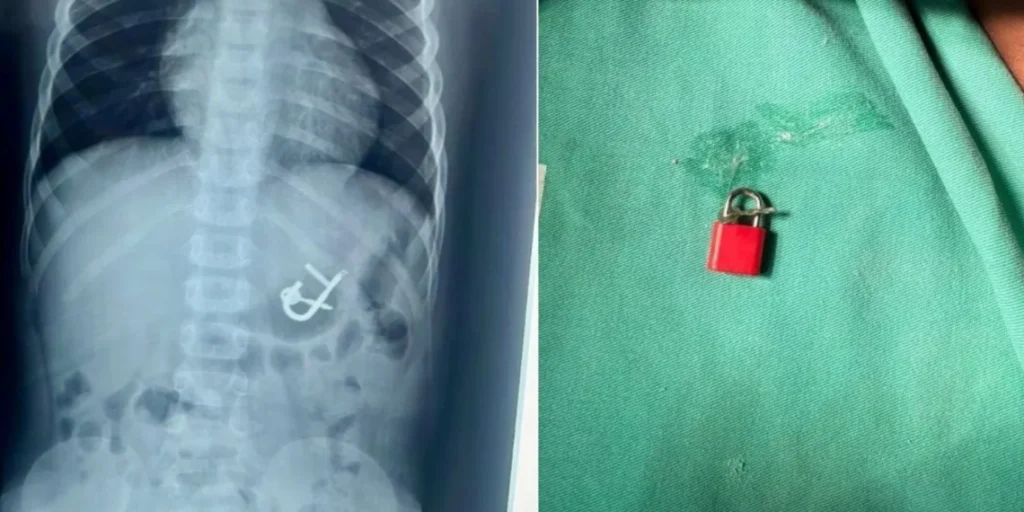

A equipe médica, composta pela Dra. Thaís Sampaio, o cirurgião de plantão, Dr. Nairton, e a anestesista Dra. Ingrid, conduziu a retirada do cadeado com sucesso. O procedimento foi realizado por meio de uma endoscopia digestiva, utilizando um dispositivo especializado para a captura do objeto.

“A retirada foi tranquila. Assim que entramos, já avistamos o cadeado no estômago, como mostrava o Raio-x. Usamos uma pinça especializada e uma cestinha, que chamamos de basket. Você tem uma pinça especializada para isso. E conseguimos retirar por via oral, sem nenhuma lesão. Não houve danos no estômago nem no esôfago, e todo o procedimento transcorreu na maior tranquilidade”, explicou a doutora Thaís Sampaio.

Após a remoção do cadeado, a criança foi liberada e recebeu alta no mesmo dia. “Normalmente, realizamos a retirada de pequenos corpos estranhos, como moedas ou partes de brinquedos. O que realmente chamou a atenção mesmo foi o tamanho do cadeado”, relatou a médica.